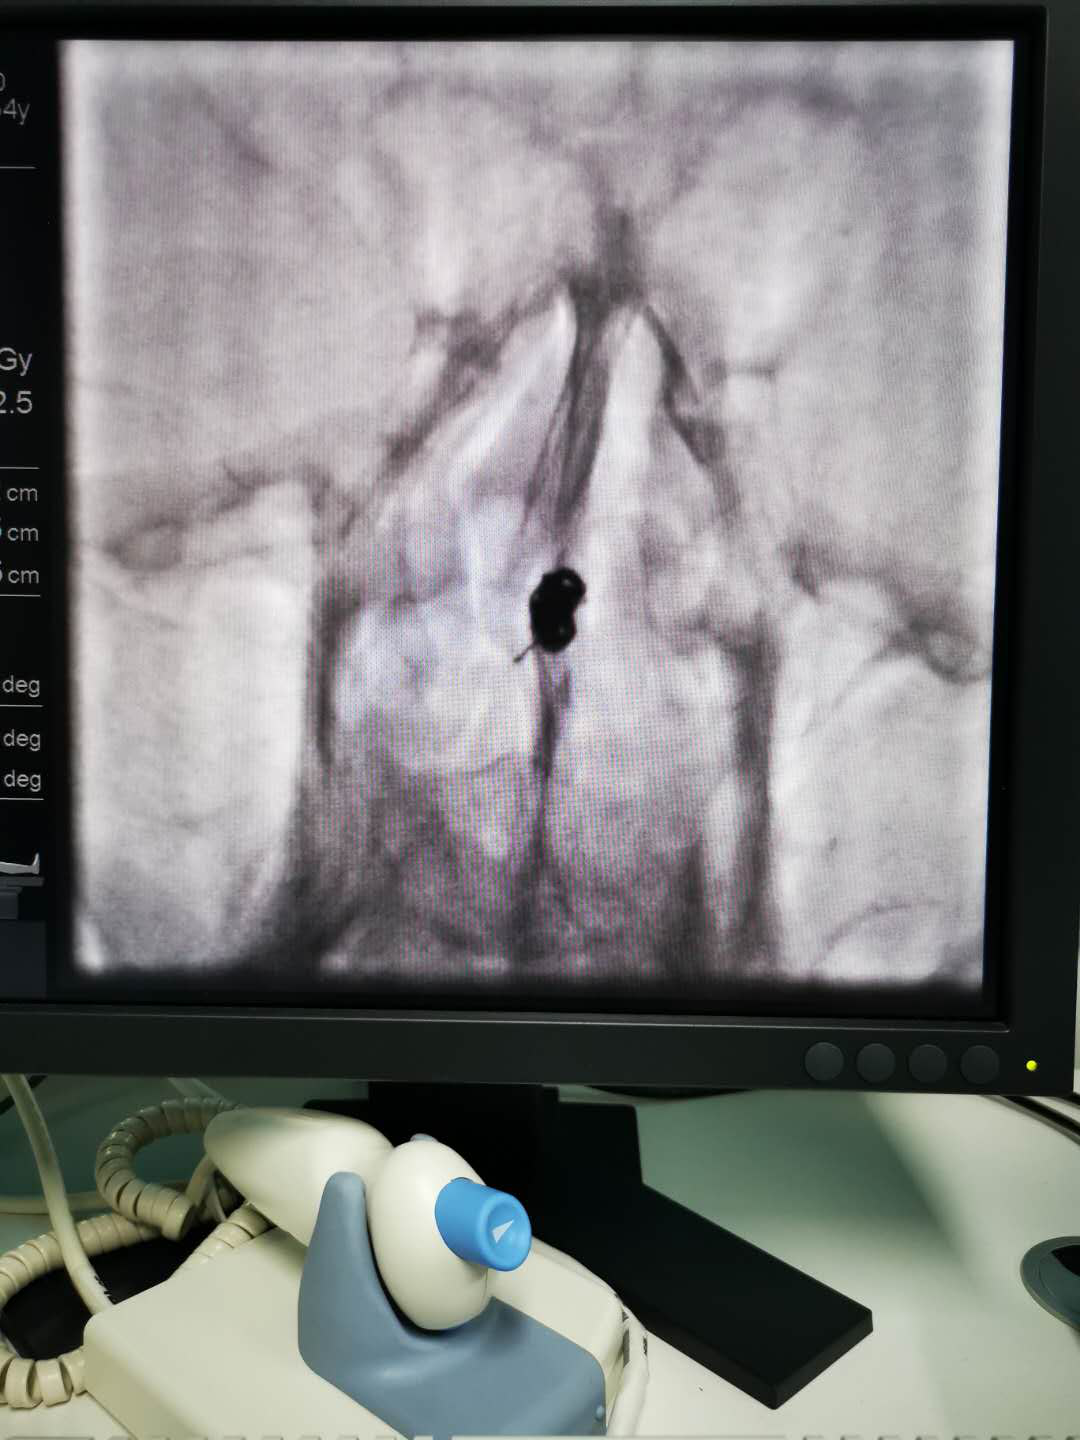

近日,我院神经外科二病区成功完成一例动脉瘤介入栓塞术。

一直以来,我院在诊疗自发性蛛网膜下腔出血方面,经验少,手段有限,患者不得不转外院治疗,以至于给患者造成巨大经济负担。自2018年神经外科二病区顺利开展了颅内动脉瘤开颅夹闭手术后,为诊治“自发性蛛网膜下腔出血伴颅内动脉瘤破裂”行开颅夹闭积累了一定经验。2019年底,我院安装了GE大型数字剪影血管造影机,主任康宏达带领科室医师积极开展新业务,新技术,目前可通过神经介入动脉瘤栓塞治疗颅内动脉瘤,为自发性蛛网膜下腔出血患者提供了另一种治疗选择。